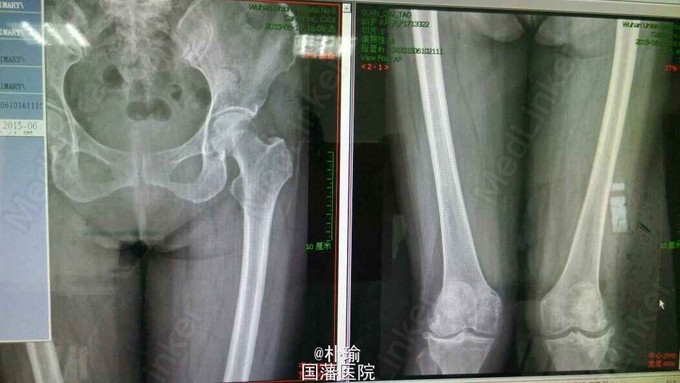

T:36.5℃,P:80次/分,呼吸:16次/分,血压130/80mmHg. 一般状态可,发育正常,表情自如,被动体位,查体合作,全身皮肤粘膜无黄染,无皮疹及皮下出血,全身浅表淋巴结未触及肿大。双肺扣诊清音,呼吸音清,未闻及明显干湿罗音及胸膜摩擦音。心率80次/分,心音未见异常。腹部平坦,未见胃肠型及蠕动波,肝脾肋下未触及。生理反射存在,病理反射未引出。 专科情况:患者双下肢肌力4-5级,左膝压痛+,反跳痛-,右膝压痛-,反跳痛-。双膝活动伸直,屈曲未见明显受限,双下肢膝跳反射,跟腱反射未见明显异常。 下肢x片:双膝胫股关节间隙变窄,外侧间隙变窄明显,关节面下骨质硬化,骨质囊变,关节边缘骨赘形成,双侧股骨内外髁边缘性骨赘并骨质浓密不均 胫骨间隙似见游离体。

根据慢性病史临床表现和X线所见,诊断为骨关节炎。 治疗方面 1.完善相关术前检查,考虑行人工关节置换术 2.NSAIDS解热镇痛 3.关节制动,嘱咐患者多注意休息